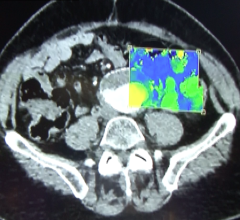

An international group of researchers report success in mice of a method of using positron emission tomography (PET) scans to track, in real time, an antibody targeting a hormone receptor pathway specifically involved in prostate cancer. This androgen receptor pathway drives development and progression of the vast majority of prostate cancers. The technique shows promise, the investigators say, as a novel way to use such an antibody to detect and monitor prostate and other hormone-sensitive cancers, as well as to guide therapy in real time.